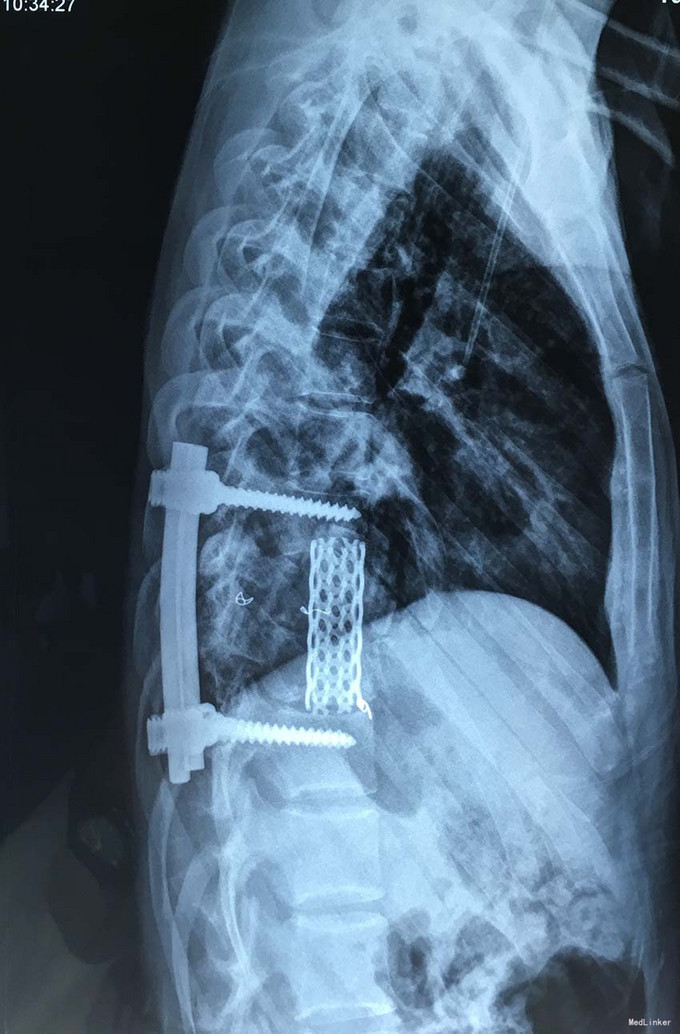

诊断:胸椎椎体肿瘤(T9-10) 治疗:先于外院行1期后路椎弓根钉固定融合手术,然后转入我院行介入下术前椎体节段血管栓塞手术,第二天行经左侧胸腔入路椎体肿瘤病灶刮除并钛网植骨植入重建手术。术后恢复满意。复查MRI显示肿瘤病灶基本完全切除。